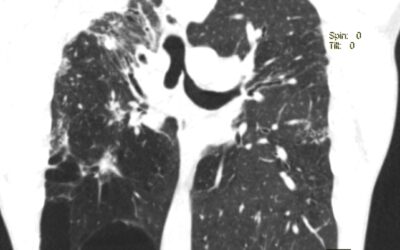

Клапанная бронхоблокация; Кровотечение из туберкулезных каверн легкого Больной 57 летний мужчина. В 2013 году был лечен по поводу туберкулеза легких. Несколько месяцев назад у него появилось кровохарканье с эпизодами кровотечения. Пациент постоянно находится на...